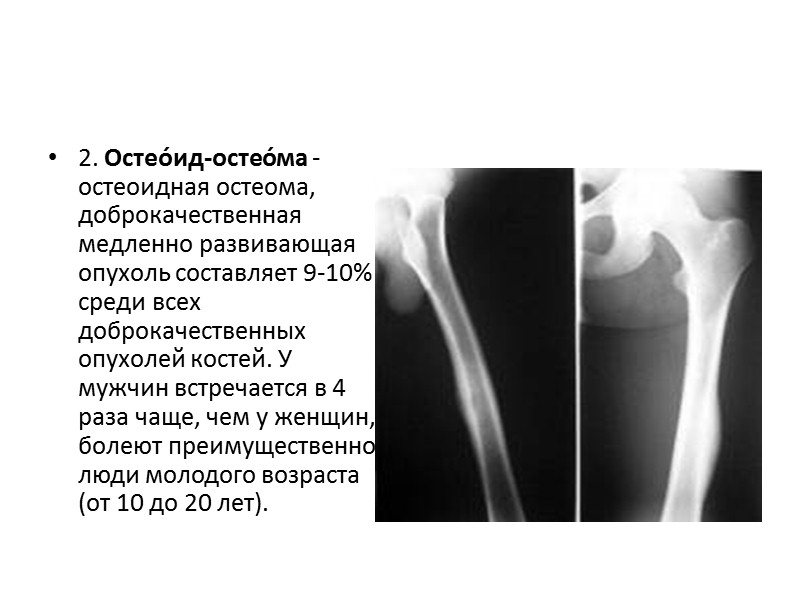

Рентгеновские снимки доброкачественных опухолей костей